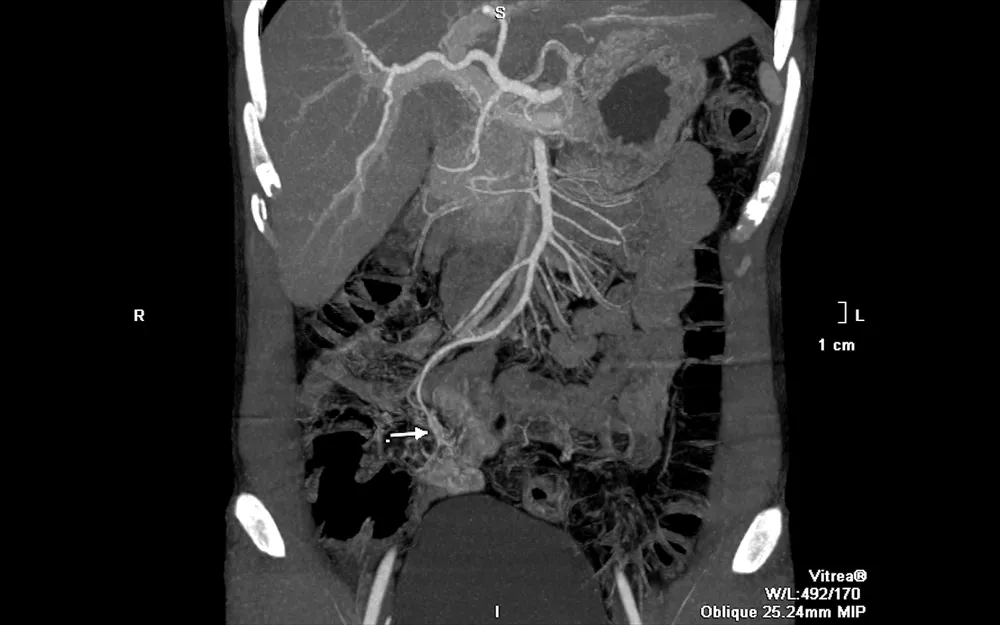

Làm gì khi nôn ói ra máu bầm liên tục? ảnh 1 Hình ảnh CT của bệnh nhân khi vào viện cho thấy mạch máu dị dạng gây chảy máu

Sau hồi sức tích cực, anh C. được tiến hành chụp cắt lớp vi tính (chụp CT) thì phát hiện búi dị dạng mạch máu từ một nhánh của động mạch mạc treo tràng trên, nằm ngay trên thành ruột non, đang có dấu hiệu chảy máu.